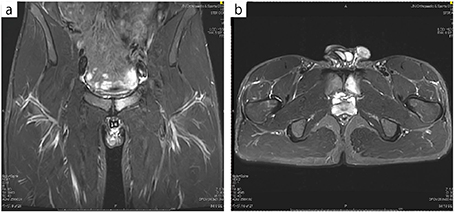

■症例2:鼠径部痛症候群に伴う恥骨浮腫

20歳,男性,サッカー選手。鼠径部痛症候群の患者で,脂肪抑制画像において左恥骨に高輝度陰影が認められた。

a:STIR coronal,TR/TE/FA:3960/40/90°,FOV:370mm,スライス厚:5mm

b:STIR axial,TR/TE/FA:4545/40/90°,FOV:350mm,スライス厚:6mm

これまでの診療において,さまざまな症例に対してMRIを撮像する中で,MRIでしか描出されない潜在性の疲労骨折など,新たな知見が得られている。鼠径部痛症候群では,MRIで恥骨部分に高輝度所見を認めても,必ずしも痛みや競技への復帰と相関しないケースがある。仁賀院長は,「問診,理学所見に基づいて,立ち合ってMRI検査ができる環境を生かして,最適な治療方法の選択やより早い競技復帰が可能になるよう,今後さまざまな検証を進めていきたいと考えています」と述べる。地域の中で最先端のスポーツ医学の成果を提供する同クリニックは,子供から高齢者までの多くの患者さん,アスリートにとって福音となるに違いない。